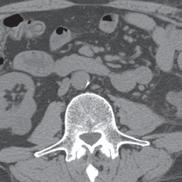

Patients who have been diagnosed with localized prostate cancer have an opportunity to seek treatment in a health care environment where every aspect of their care will be addressed. At the U-M Weiser Center for Prostate Cancer, “our focus is entirely on patient-centered care,” says co-director and prostate MRI specialist, Matthew Davenport, MD, MBA, Professor of Radiology and Urology and Vice Chair of Radiology. The center, which opened in January 2022, is the direct result of a $30 million philanthropic gift from U-M regent and prostate cancer survivor, Ron Weiser. In addition to ensuring that all patients receive world-class medical care, “we want them to feel like they’re entering a sanctuary where they’re empowered not only to survive — but to thrive. We do this by utilizing a multidisciplinary structure,” which means newly referred patients can consult with an integrated team of urologists, radiation oncologists, and radiologists, often during the same visit. This allows the Weiser team to offer different perspectives when assessing each patient’s condition, to plan the most effective treatment options.

Located in the University Hospital, the Weiser Center’s 360-degree approach is guided by two additional co-directors, Todd Morgan, MD, Professor of Urology, specializing in Urologic Oncology and Bob Dess, MD, Associate Professor of Radiation Oncology and coordinated by Program Manager, Martina Jerant, MPH. “The whole idea behind the donation was to find ways to provide high-quality comprehensive care by a team of experts,” says Dr. Dess. Through expertise, collaboration and innovation, the patient is at the center of every decision. “The amazing thing about our team is the